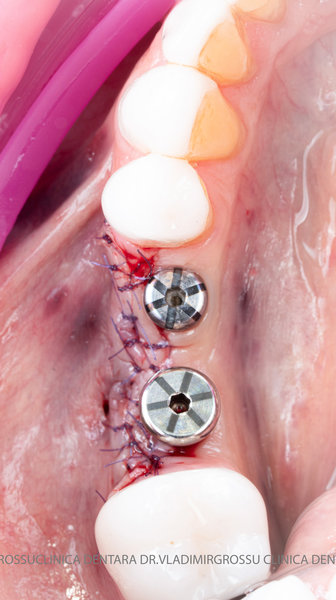

După extracția dentară, în intervalul de 6-12 luni, osul alveolar suferă un proces natural de remodelare, ceea ce conduce la scăderea volumului osos prin rezorbție. De aceea, inserția implantului dentar este ideală imediat după extracție sau, cel târziu, în primele 3-4 luni după aceasta.Scopul procedurilor de adiție osoasă este refacerea fundației osoase necesare pentru stabilizarea corectă a implantului dentar. Pentru ca un implant să reziste în timp la forțele masticatorii, este nevoie de o bază osoasă solidă și sănătoasă.

Un element esențial în procedura de aditie osoasă este utilizarea membranelor biologice, care izolează materialul osos de țesuturile moi (gingie) pe durata procesului de vindecare. Cele mai recomandate sunt membranele resorbabile din colagen sau pericard.

Adiția osoasă are un rol crucial pentru poziționarea corectă și stabilă a implanturilor dentare. Clinica stomatologică Dr. Grossu din Chișinău promovează o abordare chirurgicală estetică și predictibilă, adaptată fiecărui caz în parte.